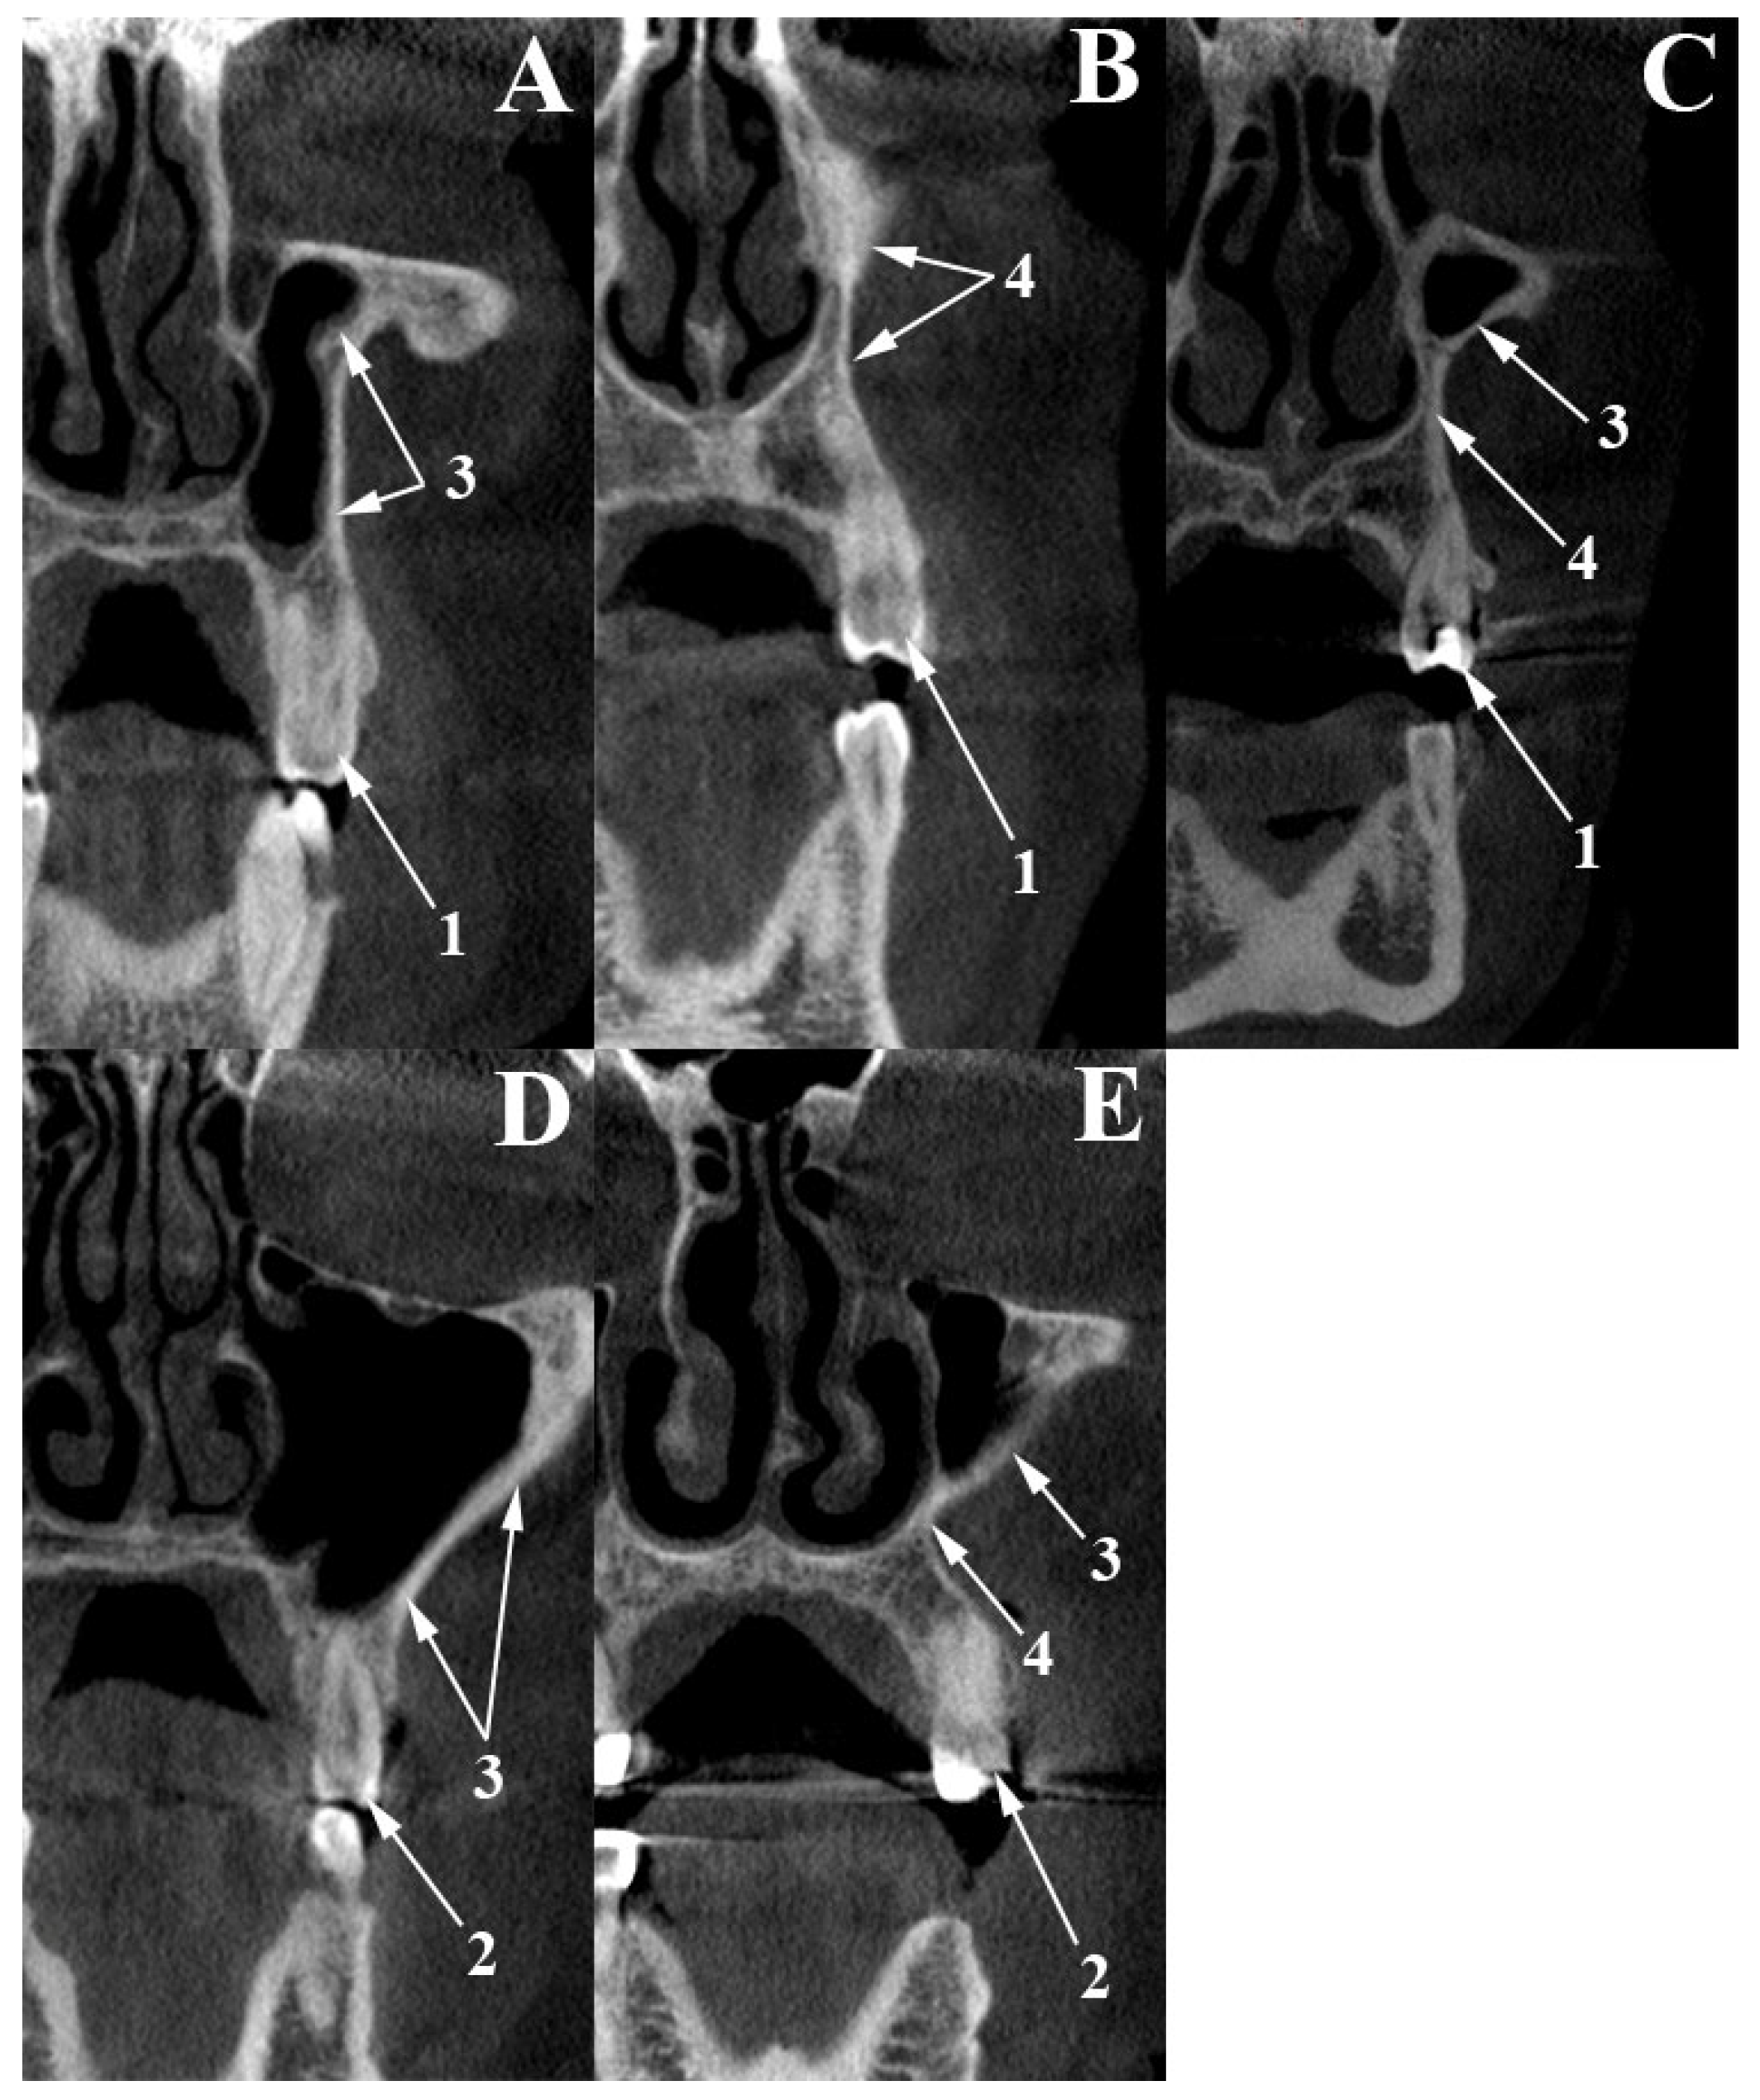

2.1. Canine Fossa Assessment

3.1. Canine Fossa